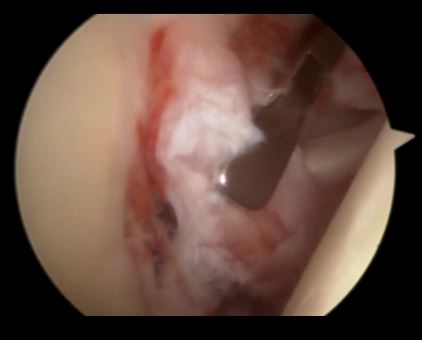

炎性肩关节——充血——滑膜炎

关节镜下可以彻底的清理关节内炎性滑膜组织及黏连带(盂肱关节及肩峰下关节)

黏连带